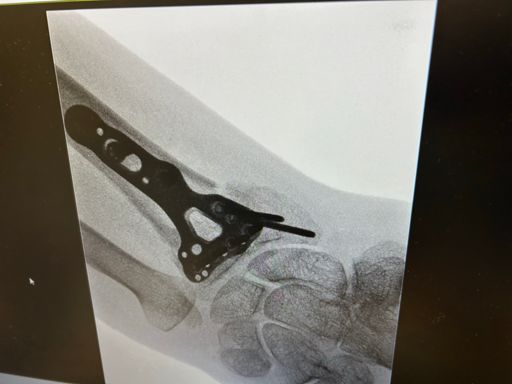

Physio on the Peloton. 2 weeks after surgery 30 min Vinyl Vault Ride with Hannah Corbin